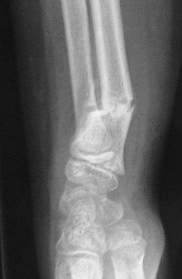

Fracture métaphysaire distale du radius : radio de Profil à J15

Déplacement secondaire à J15 de la fracture